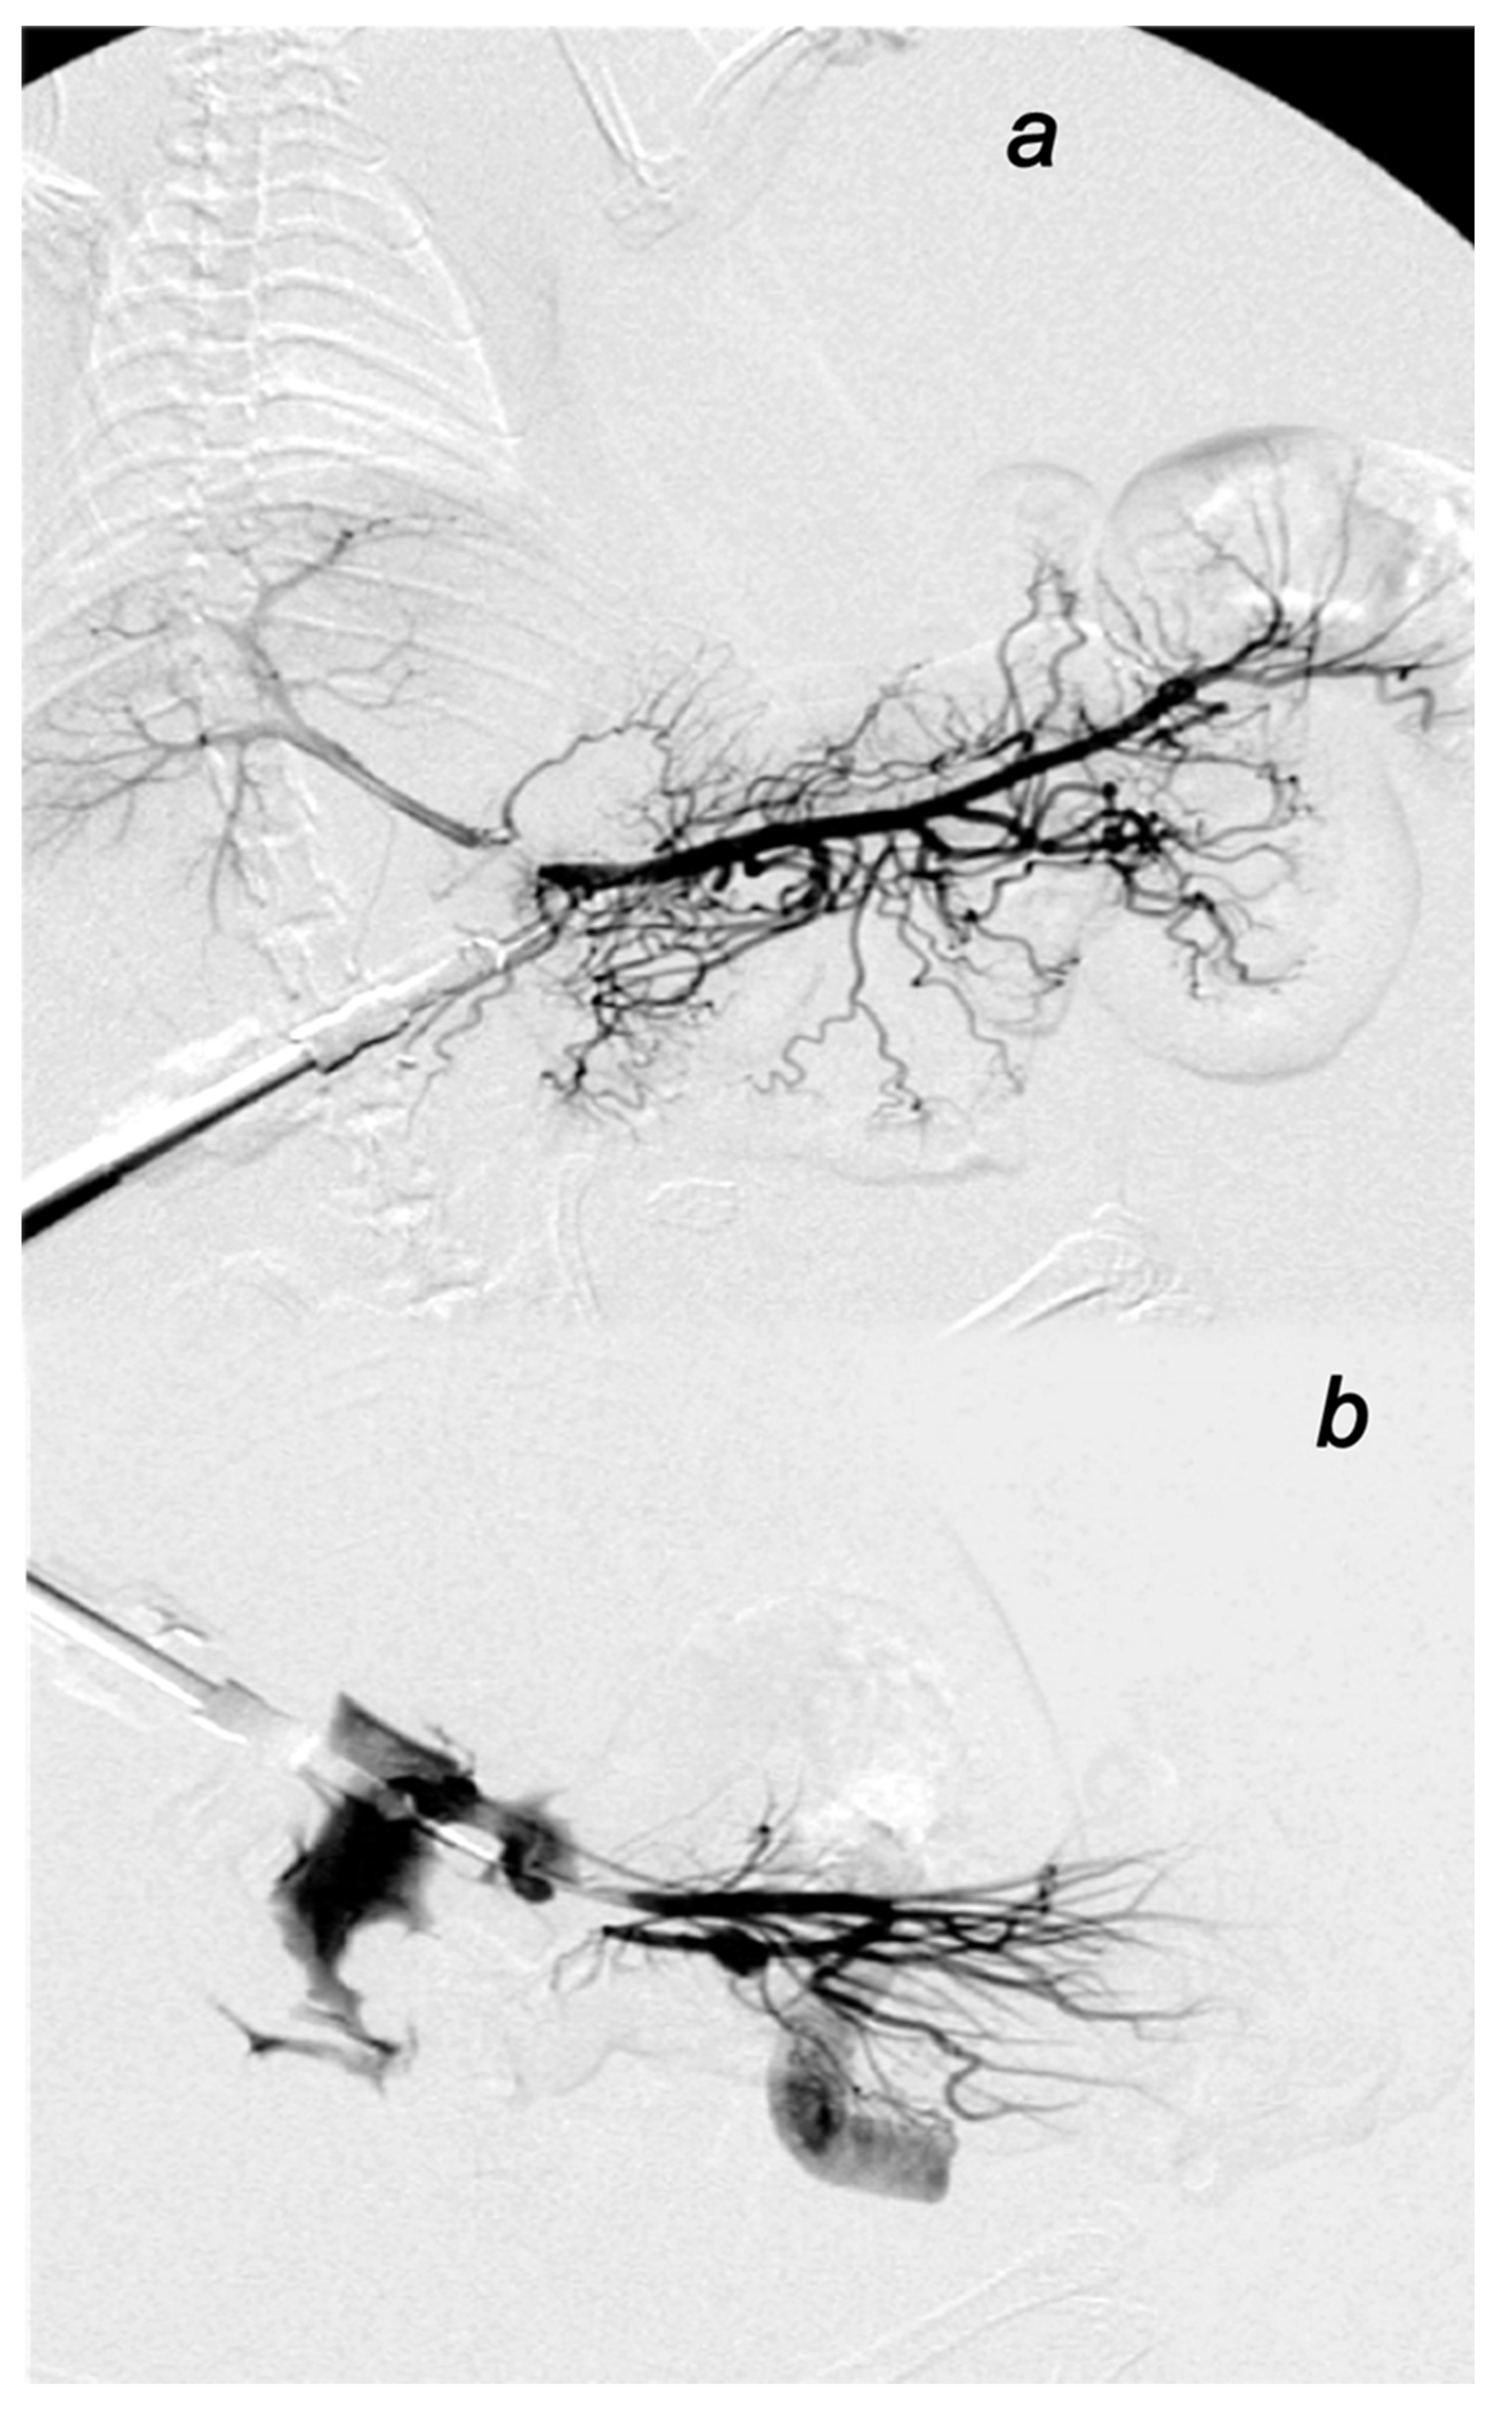

3.2.2. Venography in the Superior Mesenteric Vein